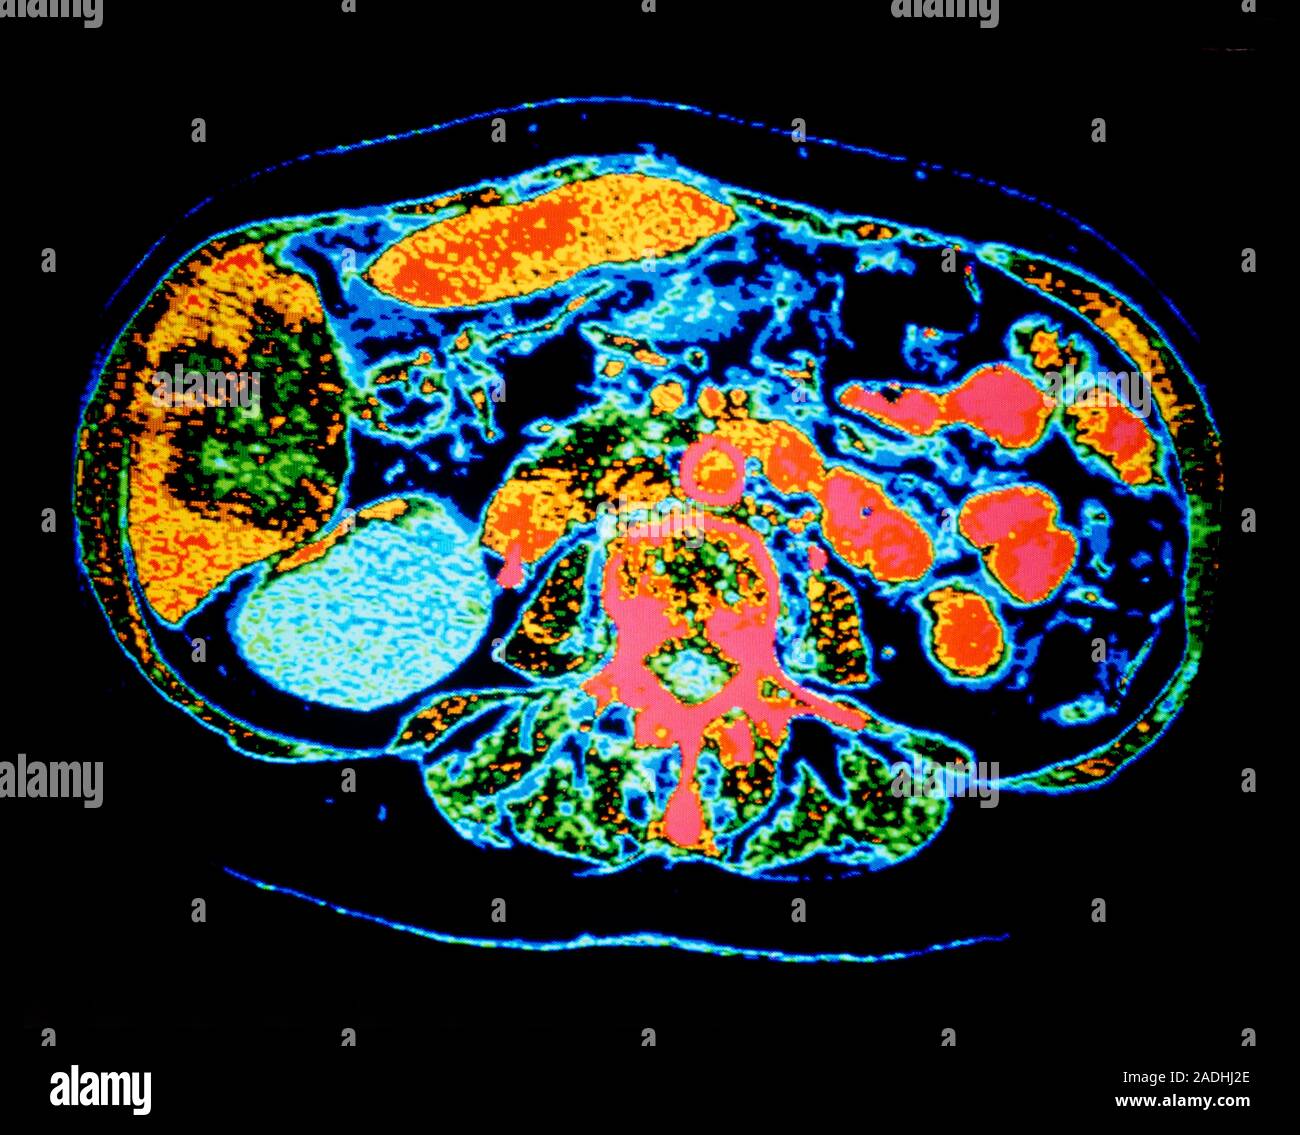

Kidney cyst. Falsecolour computed tomography (CT) scan of an axial Can A Ruptured Kidney Cyst Cause Bleeding kidney cysts may sometimes lead to complications, including: A kidney cyst may become infected, causing fever and pain. Complications of simple kidney cysts. Bedside renal ultrasound demonstrated a right renal cyst with echogenic debris consistent with a. spontaneous renal hemorrhage is an uncommon entity with potentially serious consequences. bleeding due to rupture of a cyst in autosomal. Can A Ruptured Kidney Cyst Cause Bleeding.